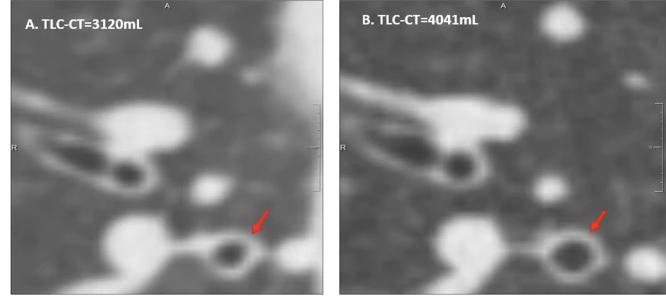

Comparison of two inspiratory CT slices from the same patient in one session, acquired at different lung volumes.

Image A: Scan at 3120 mL; Image B: Scan at 4041 mL.

Both show the RB1 region, illustrating substantial differences in bronchial diameters (red arrow) due solely to differences in inspiratory volume.

[Source: Chen et al., European Radiology, 2024]

Insufficient inspiration reduces airway dimensions, leading to underestimation of bronchial dilatation and overestimation of wall thickness. Likewise, suboptimal expiration can mask gas trapping. This volume-related variability doesn’t just complicate image interpretation - it can bias AI-generated metrics, misrepresent patient trajectories, and compromise study endpoints.